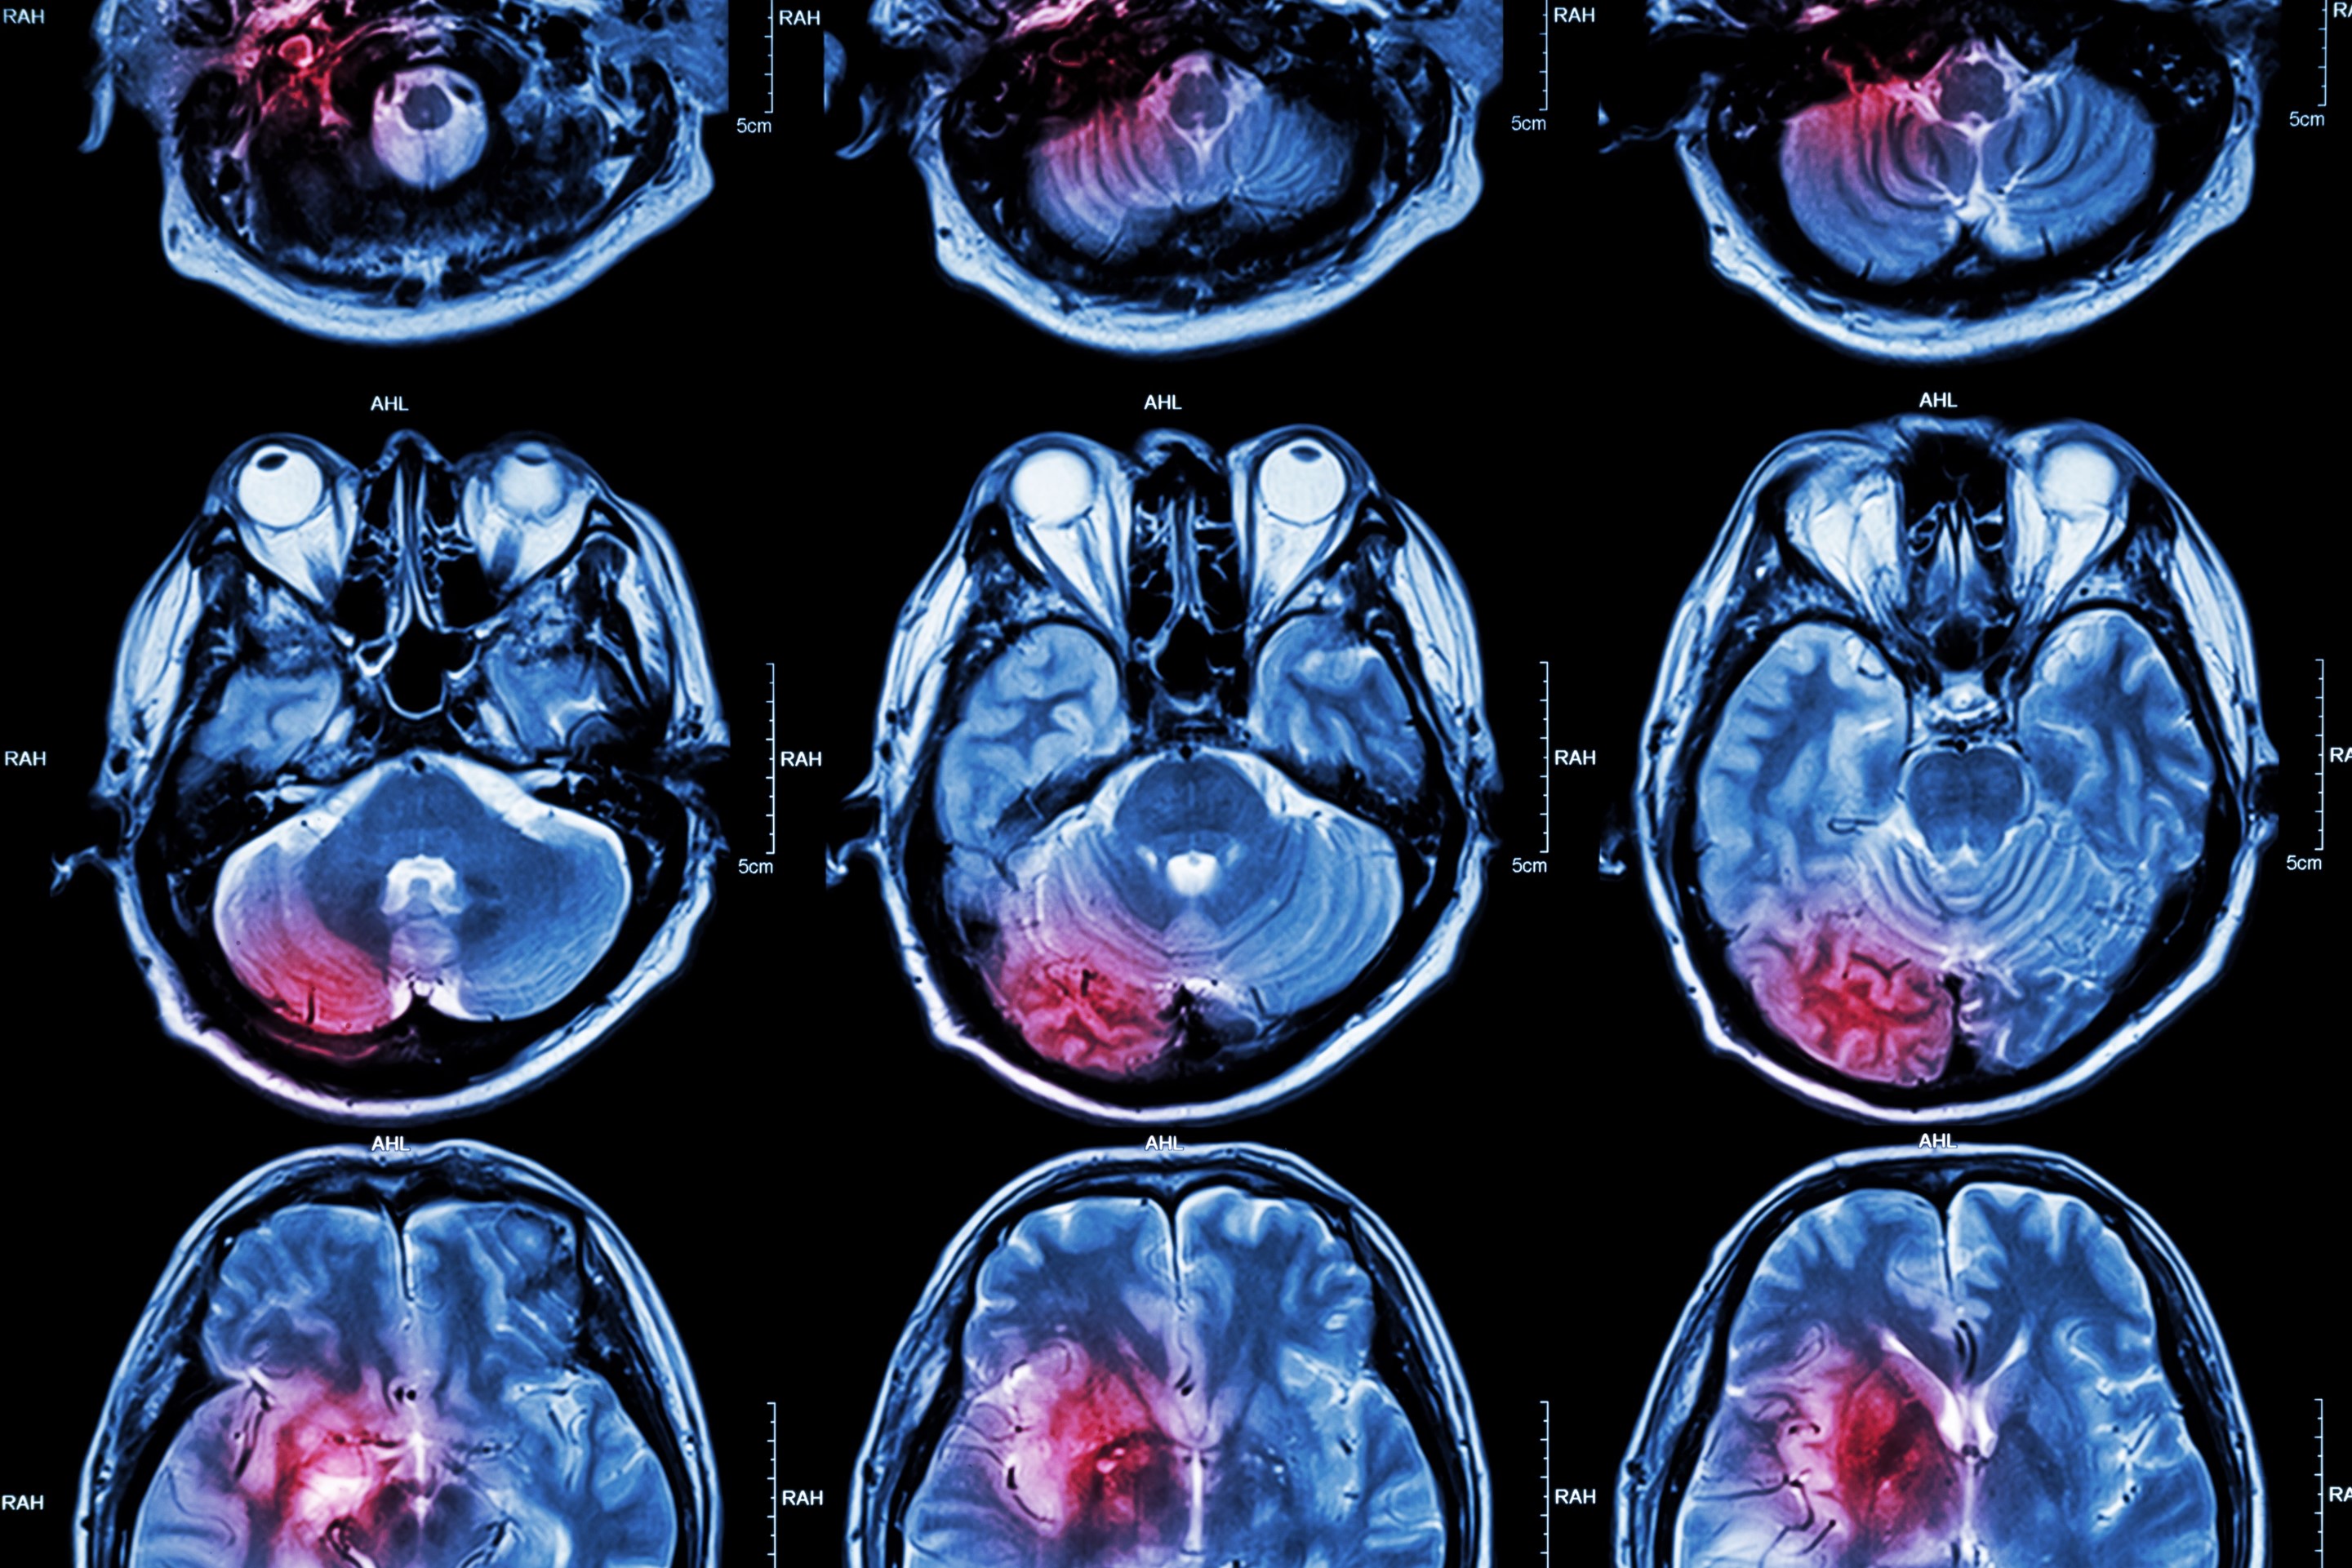

What impacts long-term cognitive decline after a stroke?

An international collaboration led by researchers from UNSW Sydney’s Centre for Healthy Brain Ageing (CHeBA) has offered new insights into what happens to cognitive function following a stroke and which risk factors lead to faster cognitive decline.

It is currently estimated that one in four people globally will have a stroke in their lifetime1, with more than 445,087 Australians currently living with the effects of stroke2.

Although post stroke loss of cognitive ability is common, the trajectory and full extent of brain changes after stroke remains unclear.